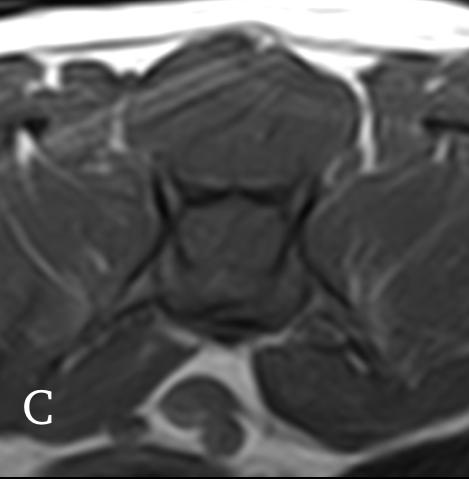

El examen neurológico evidenció paraparesia no ambulatoria y retraso en las reacciones posturales de ambas extremidades posteriores, más marcado en la extremidad posterior izquierda (EPI) (Fig.1). Los reflejos patelar, flexor y perineal estaban disminuidos y la nocicepción, intacta. El paciente presentaba parálisis de la cola con pérdida de nocicepción. La exploración de los pares craneales y las extremidades anteriores fue normal. No se detectó dolor espinal durante la evaluación. El examen neurológico fue compatible con una lesión localizada entre los segmentos espinales L4-S3.

Las pruebas diagnósticas realizadas incluyeron análisis de sangre, radiografía laterolateral de tórax y ecografía abdominal, sin resultar en alteraciones significativas. La serología frente al virus de la leucemia e inmunodeficiencia felina resultó positiva para esta última. En el estudio de resonancia magnética (RM; Fig. 2) de la región toracolumbosacra (Toshiba Vantage Elan 1.5 T: Adquisición de planos transversal, sagital y coronal ponderados en T1 pre y post-contraste intravenoso con gadolinio, así como planos ponderados en T2 y STIR) se cuentan 6 vértebras lumbares, lo cual es compatible con anatomía de transición en la región lumbar, como hallazgo incidental. En el lado izquierdo del canal vertebral, desde el tercio craneal de la vértebra L5 hasta el tercio caudal de la vértebra L6 se encuentra una lesión con aspecto alargado y de base ancha, con márgenes mal definidos e irregulares, distribución posiblemente extradural y/o intradural/extramedular, causando compresión severa de la médula espinal, que aparece desplazada hacia el lado derecho. En cuanto al patrón de intensidad de la señal, este fue hiperintenso de forma homogénea en las secuencias ponderadas en T2 e isointenso en las secuencias ponderadas en T1, con un realce homogéneo y focal en la región media de la vértebra L6. La lesión se extiende parcialmente en el foramen intervertebral izquierdo entre las vértebras L5 y L6 y se aprecia siringomielia leve, que puede ser un proceso secundario a la compresión de la médula espinal por parte de la lesión, más caudalmente a nivel lumbar.

Figura 2. Imágenes de RM postcontraste en las que se identifica una lesión de forma alargada y ancha en su base, con distribución posiblemente extradural y/o intradural/extramedular a nivel de la vértebra L6 (flechas rojas). (A) Secuencia dorsal en STIR. (B) Secuencia transversal en T2. Nótese la compresión severa a la que es sometida la médula espinal (flecha verde). (C) Secuencia transversal en T1 precontraste. (D) Secuencia transversal en T1 postcontraste. M: masa; SC: médula espinal; R: derecha; L: izquierda.